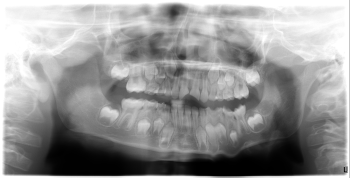

The following Monday, my grandson was in my Auburn Hills office. His X-rays showed incompletely formed roots—a critical factor in planning treatment. Intraoral evaluation revealed that the pulp chambers were open, exposing vital tissue and vessels, but with no bleeding (Figs. 1–3).

At this stage, many clinicians might consider endodontic therapy. However, performing endo on an immature tooth can disrupt normal root development. My goal was to protect the pulp and preserve vitality long enough for continued root formation.